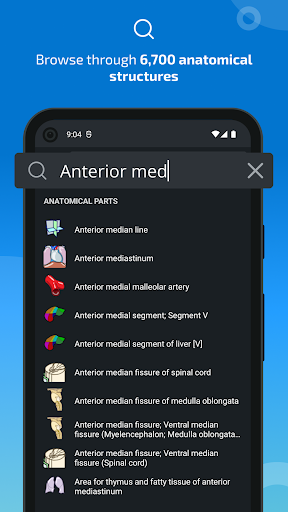

- Mudah menemukan struktur anatomi berkat pencarian indeks

*Temukan bagian anatomi Anda dengan lebih mudah berkat fitur pencarian baru yang lebih intuitif dan canggih